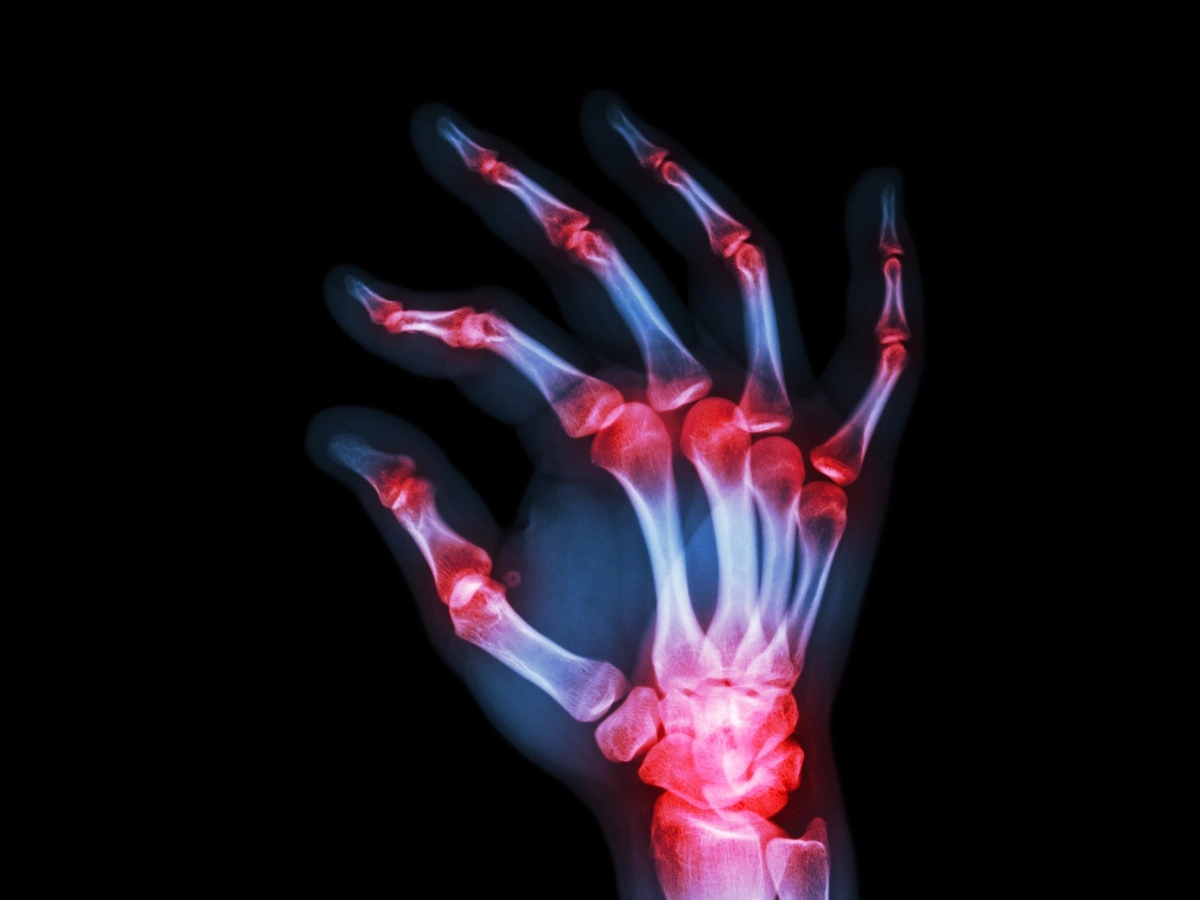

손가락 관절염 증상

- 손가락을 움직일 때 '딱' 소리가 난다

- 손가락이 시리고 붓는다

- 손가락 마디에 콕콕 쑤시는 듯한 통증이 있다

- 손가락 끝 마디에 통증이 느껴진다

- 손가락을 굽히고 펴는 것이 불편하다

- 손가락 관절에 열감이 느껴진다

- 관절의 움직임이 둔해진 느낌이 든다

- 아침에 일어났을 때 손이 부어있거나 홍반이 있다

손가락 관절염은 초기에는 증상이 약한 경우가 많고 휴식을 취하거나 손 사용을 자제할 경우 통증이 가라앉기도 하기 때문에 조기 치료 시기를 놓치게 되는 경우가 많습니다.

그러나 초기 증상이 있을 때 적절한 치료를 하지 않는다면 병이 커져 치료가 힘들어지거나 영구적 장애를 일으킬 수도 있습니다.

따라서 위 증상들 중 해당하는 증상이 있는 경우, 병원에 방문하여 치료에 대한 방향을 상담해 보는 것이 좋습니다.